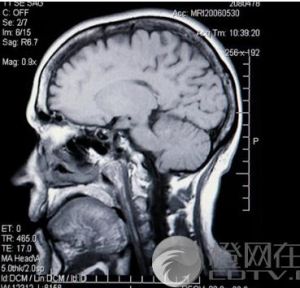

腦脊液腦脊液檢查指穿刺後測得的腦脊液壓力,側臥位成人為0.78-1.76kPa(80-180mm水柱),兒童為0.39-0.98kPa(40-100mm水柱)...

正常值 臨床意義 注意事項 檢查過程 相關疾病腦脊液(cerebrospinalfluid),通常用其縮寫形式CSF來表示。腦脊液是由腦室內脈絡叢產生的一種無色透明的液體,它循環流動於腦和脊髓表面,...

臨床意義 正常值考範圍腦脊液(cerebrospinal fluid,CSF)主要由腦室中的脈絡叢所分泌,腦脊液不斷產生又不斷被吸收回流至靜脈,在中樞神經系統起著淋巴液的作用...